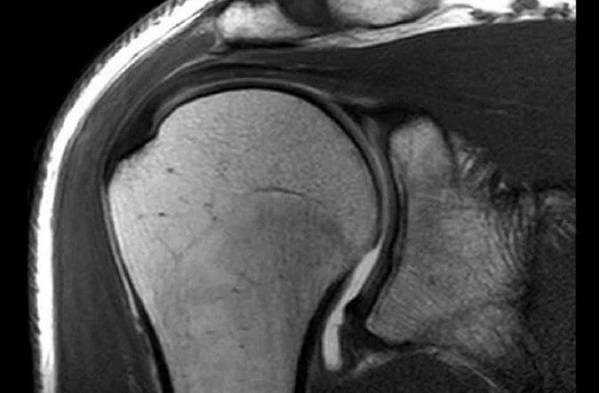

Плечевой сустав на МРТ

Артрит правого тазобедренного сустава на снимке МРТ

Магнитно-резонансное сканирование тазобедренных суставов